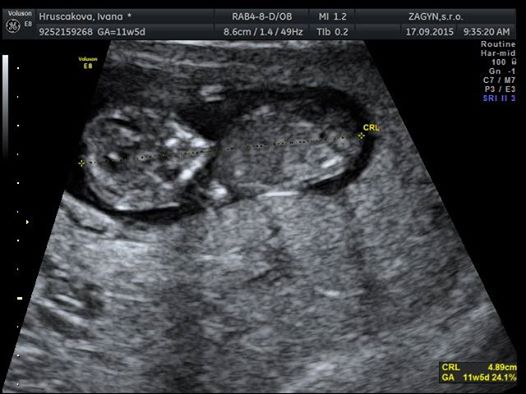

Bol júl a chystali sme sa na dovolenku do maďarska so švagrovcami a ich rodinami.Všetko bolo ok,akurat som si všimla,že som nejako viac unavená, ale nejako som to neriešila.ešte na dovolenke som si so švagrinou robila srandu že čo ak prídeme domov a zistím že som tehotná.HAHA.Nejak som tomu neverila.Ale mala som pravdu..keď prišiel deň kedy som to mala dostať ale nič sa nedialo už som vedela,že asi niesom sama☺na druhý deň som si išla kupiť test,ktorý mi to potvrdil,ale zatiaľ som manželovi nič nehovorila.chcela som to mať najprv potvrdené doktorom.Keďže ja som veľmi netrpezlivý človek išla som k dr.hneď o 2dni.Na UTZ sa už namňa usmievala malá bodka-naša Bianka💗veľmi netrpezlivo som čakala kým pride manžel z práce aby som mu mohla oznámiť novinu.Mala som aj menšie obavy,ani neviem prečo.Veľmi veľmi sa tešil☺